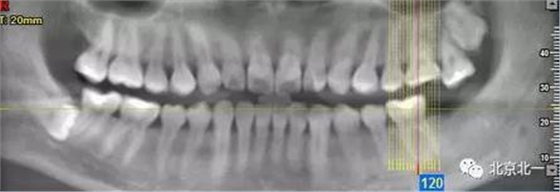

病例資料:一般情況,患者女性,28歲, 主訴:要求拔右側下頜智齒,檢查:右側下頜第三磨牙未見萌出, 拍片如圖。

圖一:CBCT顯示右側下頜水平骨埋伏牙,牙冠距離下牙槽神經管接近。